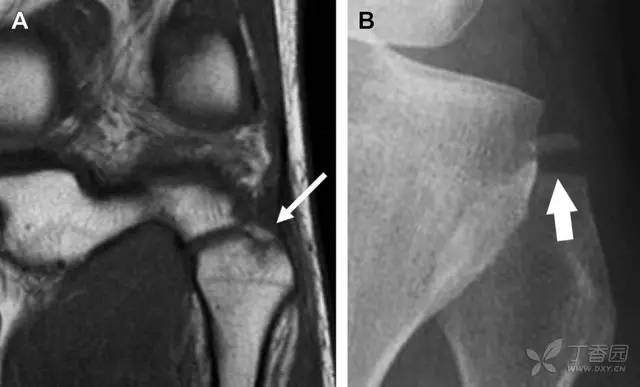

9 股骨外侧髁凹陷征

图 2 扭伤后的股骨外侧髁凹陷征

A 侧位片示股骨外侧髁凹陷。B MRI 矢状位 T2 加权像示股骨外侧髁及胫骨后外侧骨挫伤(空箭头)。胫骨近端随着后交叉韧带撕裂发生移位,露出外侧半月板的后角(弧形箭头)。